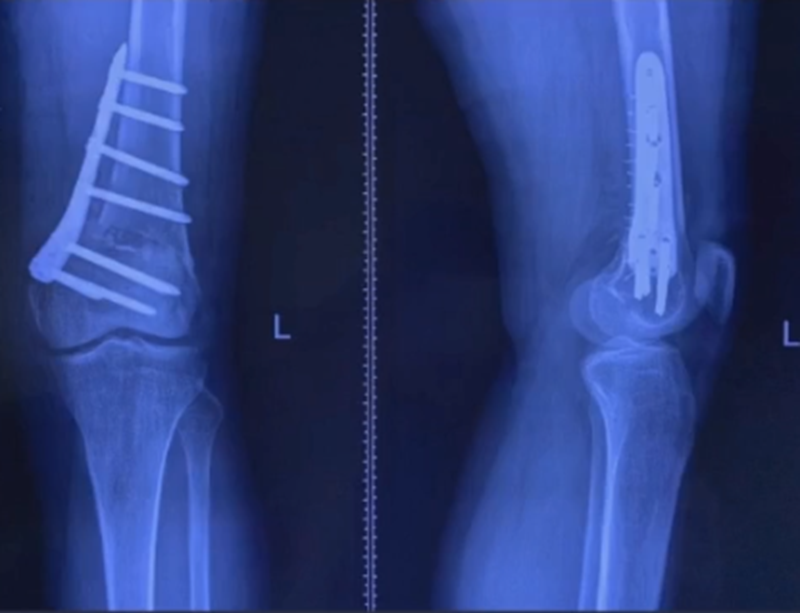

病例,X患者,女,双侧外翻膝,行双侧DFO。

术后6周摔伤,一侧出现膝内翻。

影像学检查显示左侧出现合页断裂。

进行翻修,术前力线显示内翻。